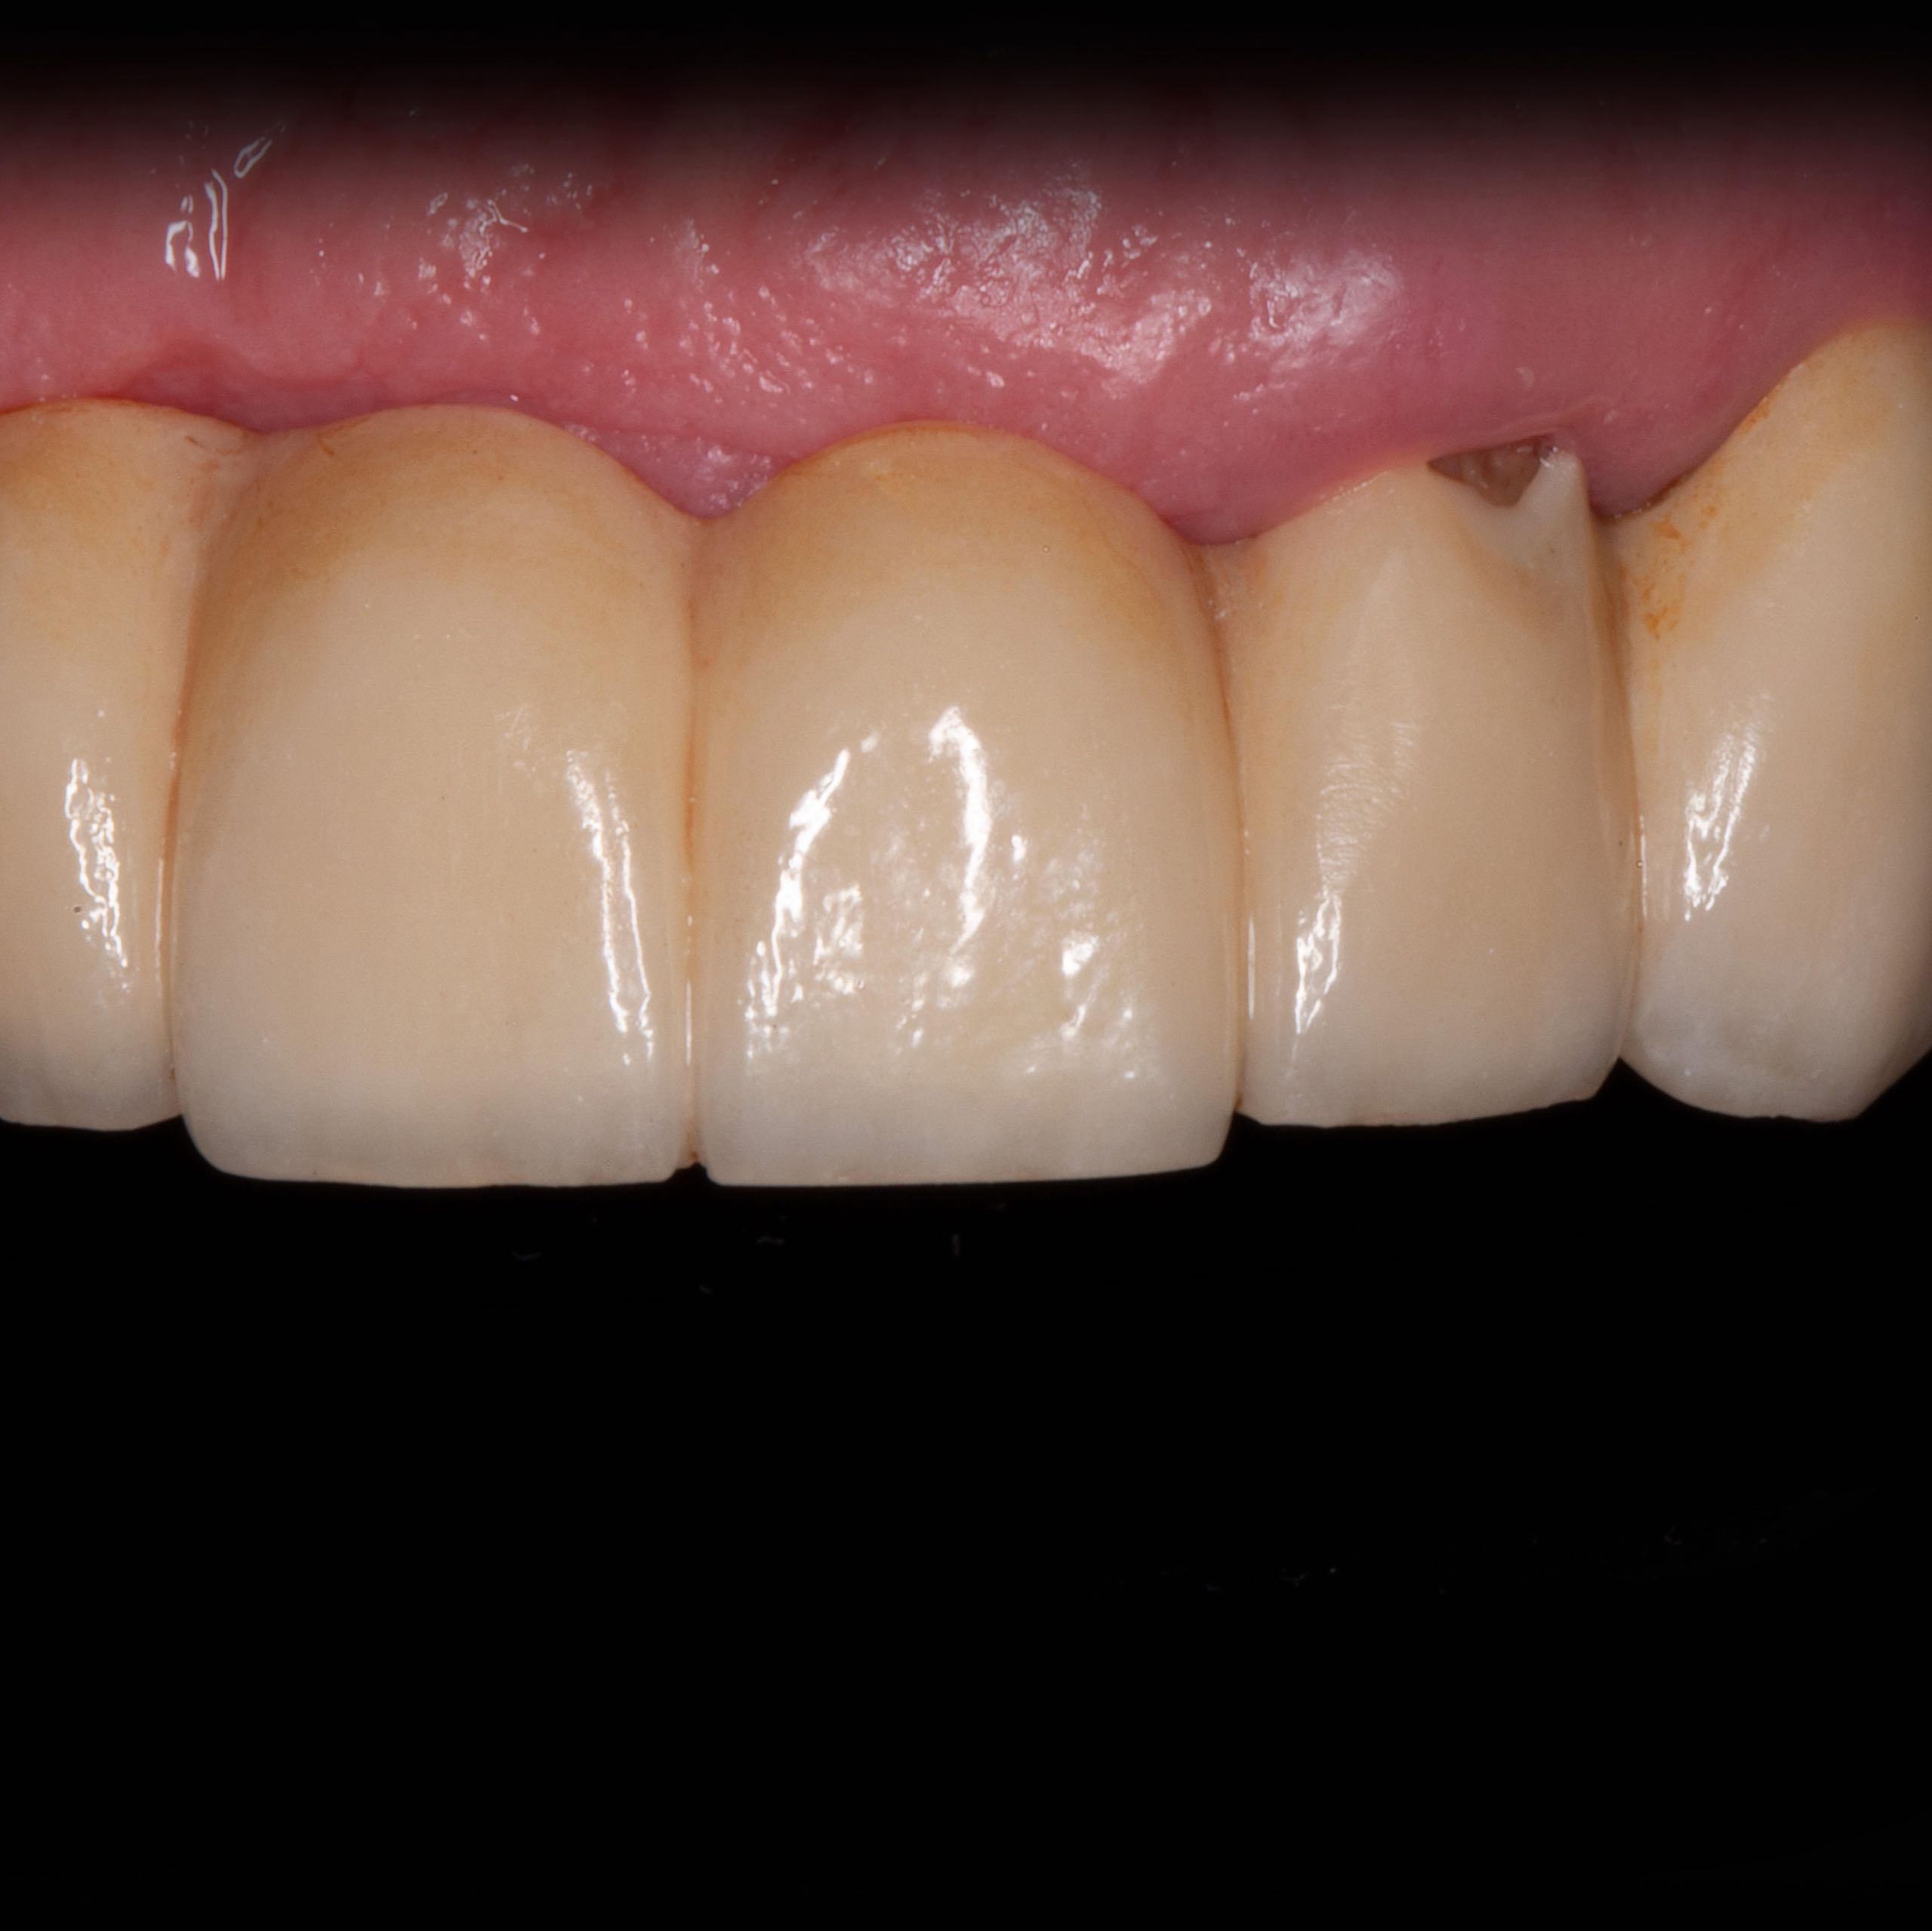

Reparatur und Wiederherstellung der Krone am linken seitlichen Schneidezahn

VORHER

NACHHER

Die Arbeit ist seit 4 Jahren beständig